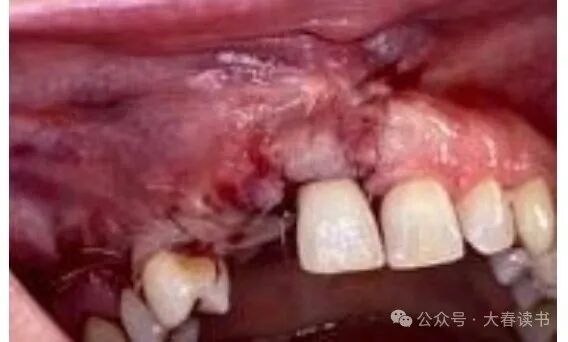

Figure 6: Intraoral view: a, Insufficient alveolar bone width, defect reaching the apex of adjacent teeth. b, Flap exposing the defect area.